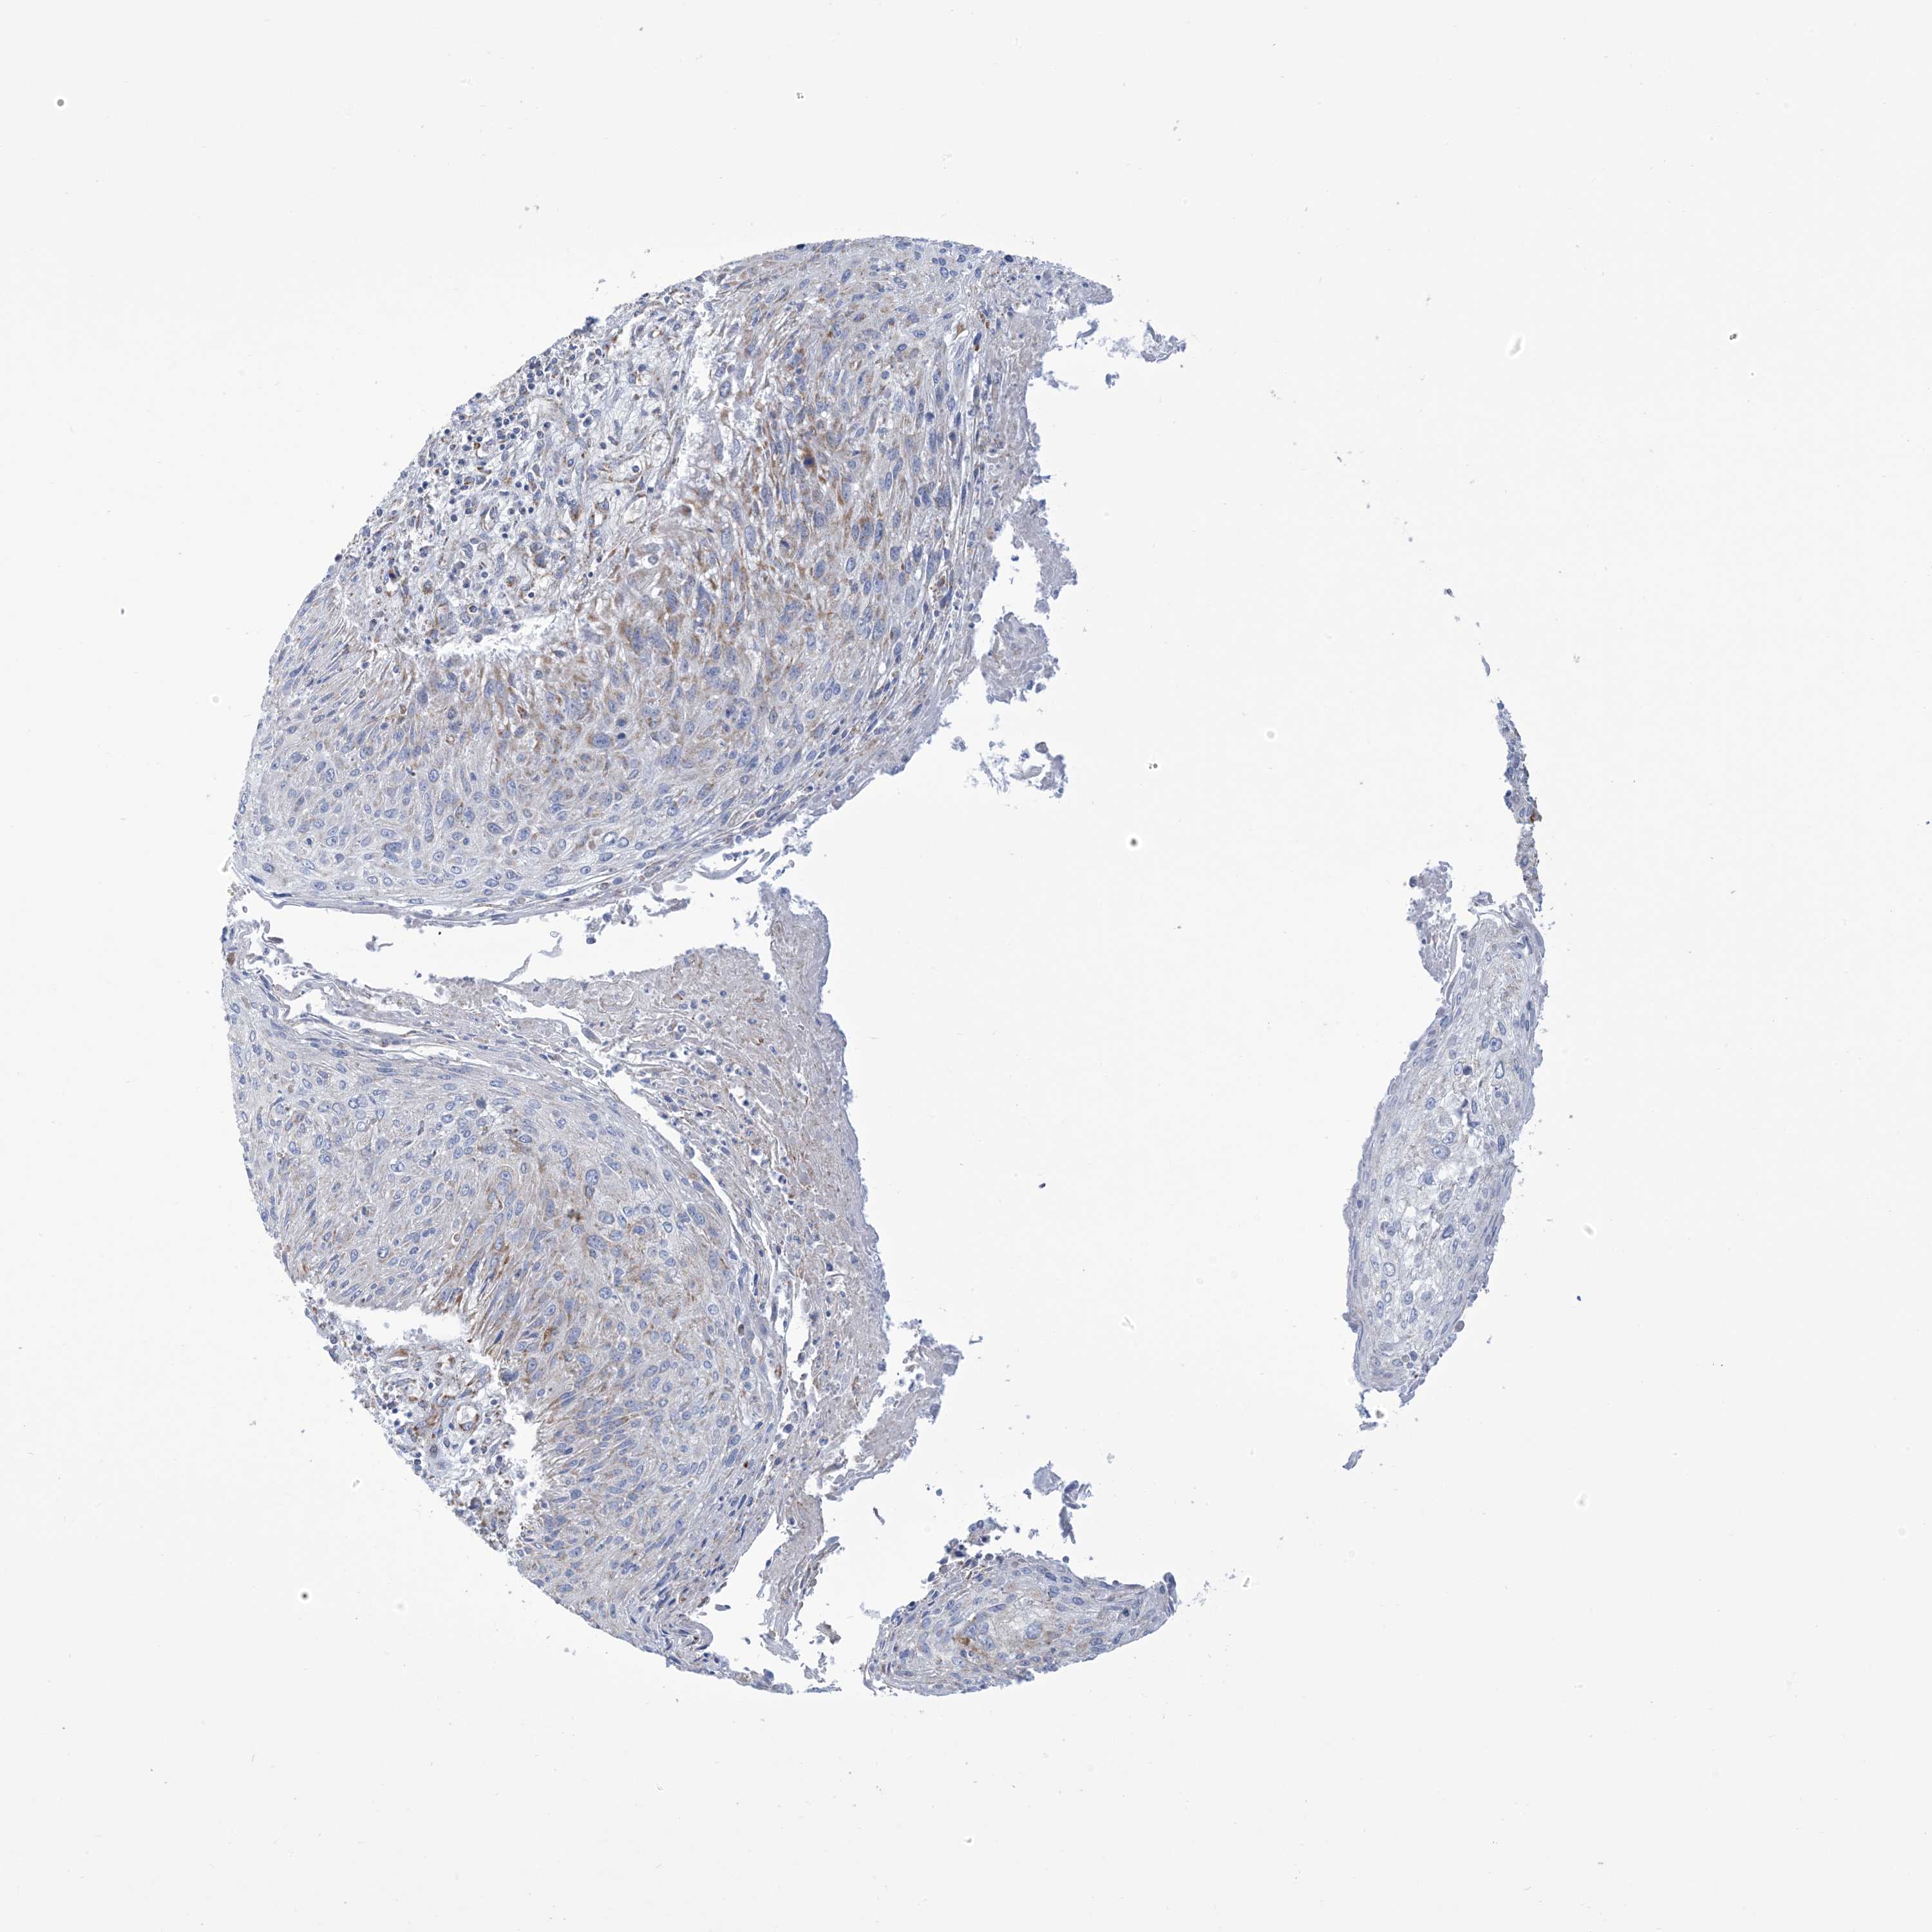

CERVICAL CANCER - Protein expressioni

A mouse-over function shows sample information and annotation data. Click on an image to view it in a full screen mode. Samples can be filtered based on level of antibody staining by selecting one or several of the following categories: high, medium, low and not detected. The assay and annotation is described here.

Note that samples used for immunohistochemistry by the Human Protein Atlas do not correspond to samples in the TCGA dataset.

Antibody stainingi

Antibody staining in the annotated cell types in the current human tissue is reported as not detected, low, medium, or high, based on conventional immunohistochemistry profiling in selected tissues. This score is based on the combination of the staining intensity and fraction of stained cells.

Each image is clickable and will lead to virtual microscopy that enables deeper exploration of all samples and also displays staining intensity scores, fraction scores and subcellular localization as well as patient and tissue information for each sample.

Antibody HPA034537

Staining

High

Medium

Low

Not detected

Intensity

Strong

Moderate

Weak

Negative

Quantity

>75%

75%-25%

<25%

None

Location

Nuclear

Cytoplasmic/membranous

Cytoplasmic/membranous,nuclear

Squamous cell carcinoma, NOS

Adenocarcinoma, NOS